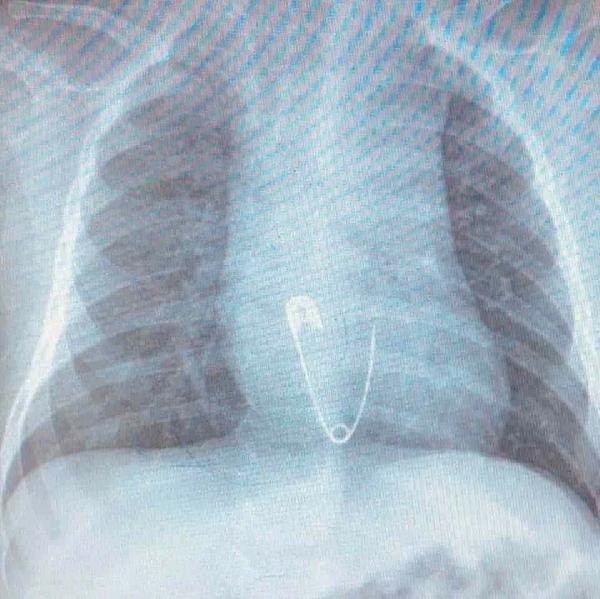

ELAZIĞ Fırat Üniversitesi'nde, 5 aylık Efraim Solmaz'ın yuttuğu kıyafetindeki çengelli iğne, yapılan endoskopi işlemiyle yemek borusundan çıkarıldı.

Efraim bebek, buradan Elazığ Fırat Üniversitesi Hastanesi'ne sevk edildi. Burada yapılan endoskopi işlemiyle bebeğin yemek borusundaki çengelli iğne çıkarıldı. Tedbir amacıyla hastanede gözlem altında tutulan Efraim bebek, daha sonra taburcu edildi.

Fırat Üniversitesi Çocuk Gastroenteroloji Hepatoloji ve Beslenme Bilim Dalı Başkanı Prof. Dr. Yaşar Doğan, Efraim bebeğin yemek borusuna takılan çengelli iğneyi 15 dakikada çıkardıklarını söyledi. Çocukların kıyafetlerine iliştirilen materyallerin büyük tehlike oluşturabileceği uyarısında bulunan Prof. Dr. Doğan, "5 aylık bebek, bize Diyarbakır'dan gönderildi. Çocuk, üzerindeki nazar boncuğu ve çengelli iğneyi ağzına atmış. O esnada ailenin müdahalesi ile nazar boncuğu çıkarılmış fakat çengelli iğneye müdahale edememişler, yemek borusuna kaçmış. Hemen müdahale ettik. Yaklaşık 15 dakikalık işlem ile başarılı bir şekilde iğne çıkarıldı. Ailelerden ricamız, çocukların üzerine tehlike arz edebilecek herhangi bir cisim takmamaları ve etrafında bulundurmamaları. Kazara böyle bir şey olursa ilk müdahale ile ilgili bilgileri varsa hızlı bir şekilde çıkarmaları ama ulaşamayacakları bir mesafede ise en kısa zamanda sağlık kuruluşuna başvurmaları. Son 1 ayda en fazla para olmak üzere kolye, broş, küpe, yüzük, bilye gibi şeyler çıkardık. Bizim için en tehlikelisi mıknatıs; çünkü bağırsaklarda yapışıklığa neden olur. Cerrahi müdahale ile erken dönemde çıkarılması lazım. Geç kalındığı zaman bağırsak nekrozlarına neden olabiliyor. Çocukların etrafında oyuncak amaçlı mıknatısların bulundurulmaması gerekiyor" diye konuştu.